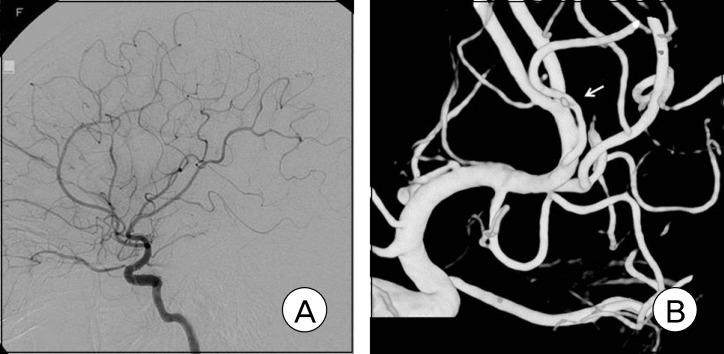

Intracranial pial arteriovenous fistula (AVF) is a rare cerebrovascular malformation, which has a single or multiple arterial connections to a single venous channel without intervening nidus, and is different from arteriovenous malformation (AVM). We report on a case of a surgically treated pial AVF. A 15-year-old girl with an altered mental state was brought to our hospital. Computed tomography (CT) showed a subcortical hematoma of approximately 24 ml in her right temporal lobe. Cerebral angiography showed an AVF supplied by the right middle cerebral artery with early drainage into the Sylvian vein and the vein of Labbe. She underwent surgical treatment with feeding artery obliteration using a clip and hematoma removal. The patient was discharged without neurologic deficits. Despite the rarity of pial AVF, for correct diagnosis and treatment, neurosurgeons should recognize this condition. Pial AVF can be managed simply by disconnection of the shunt by surgery or endovascular treatment, and a good result can be achieved.

颅内软膜动静脉瘘(AVF)是一种罕见的脑血管畸形,它有一条或多条动脉与单一静脉通道相连,其间无异常血管团,与动静脉畸形(AVM)不同。我们报告一例经手术治疗的软膜AVF病例。一名精神状态改变的15岁女孩被送至我院。计算机断层扫描(CT)显示其右侧颞叶有一个约24毫升的皮质下血肿。脑血管造影显示一个由大脑中动脉供血的AVF,早期引流至大脑外侧裂静脉和Labbe静脉。她接受了使用夹子闭塞供血动脉并清除血肿的手术治疗。患者出院时无神经功能缺损。尽管软膜AVF罕见,但为了正确诊断和治疗,神经外科医生应认识到这种疾病。软膜AVF可通过手术或血管内治疗简单地断开分流来处理,并可取得良好效果。